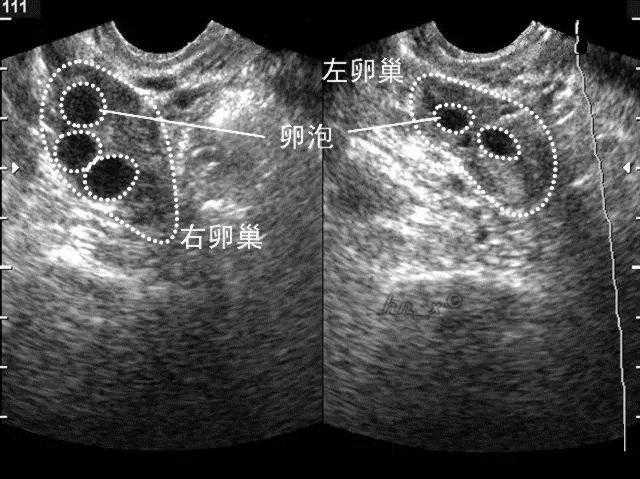

3、监测卵泡发育

打过促排卵针之后,女性需要定期到医院监测卵泡发育,通过仪器观察卵泡的形态,在最合适的阶段将卵细胞取出。